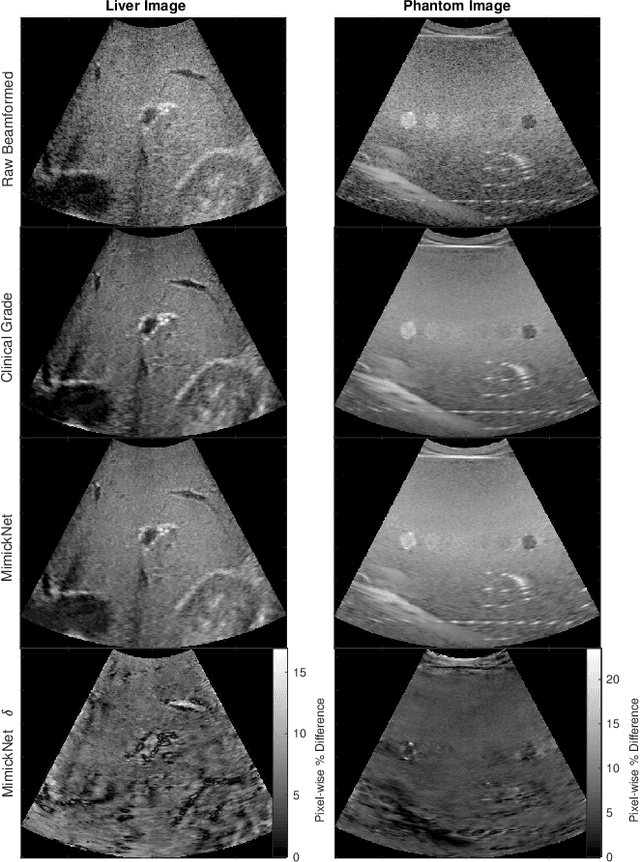

Abstract:Image post-processing is used in clinical-grade ultrasound scanners to improve image quality (e.g., reduce speckle noise and enhance contrast). These post-processing techniques vary across manufacturers and are generally kept proprietary, which presents a challenge for researchers looking to match current clinical-grade workflows. We introduce a deep learning framework, MimickNet, that transforms raw conventional delay-and-summed (DAS) beams into the approximate post-processed images found on clinical-grade scanners. Training MimickNet only requires post-processed image samples from a scanner of interest without the need for explicit pairing to raw DAS data. This flexibility allows it to hypothetically approximate any manufacturer's post-processing without access to the pre-processed data. MimickNet generates images with an average similarity index measurement (SSIM) of 0.930$\pm$0.0892 on a 300 cineloop test set, and it generalizes to cardiac cineloops outside of our train-test distribution achieving an SSIM of 0.967$\pm$0.002. We also explore the theoretical SSIM achievable by evaluating MimickNet performance when trained under gray-box constraints (i.e., when both pre-processed and post-processed images are available). To our knowledge, this is the first work to establish deep learning models that closely approximate current clinical-grade ultrasound post-processing under realistic black-box constraints where before and after post-processing data is unavailable. MimickNet serves as a clinical post-processing baseline for future works in ultrasound image formation to compare against. To this end, we have made the MimickNet software open source.